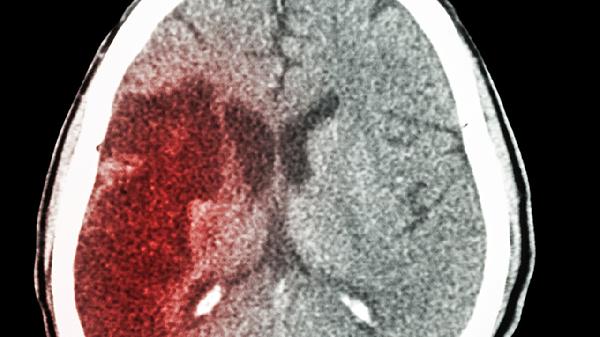

脑出血的患者常常会突然出现剧烈头痛、恶心呕吐、意识模糊或身体一侧无力,这些症状会根据出血的位置和量有所不同。常见的体征有血压迅速上升、两侧瞳孔大小不一、病理反射阳性,严重时甚至可能出现脑疝。通过影像检查可以发现大脑内部有高密度的出血区域,治疗上需要及时降低颅内压力,必要时进行手术清除血肿,常用的药物包括甘露醇注射液、呋塞米注射液来减轻脑水肿,以及氨甲环酸注射液来防止再次出血。